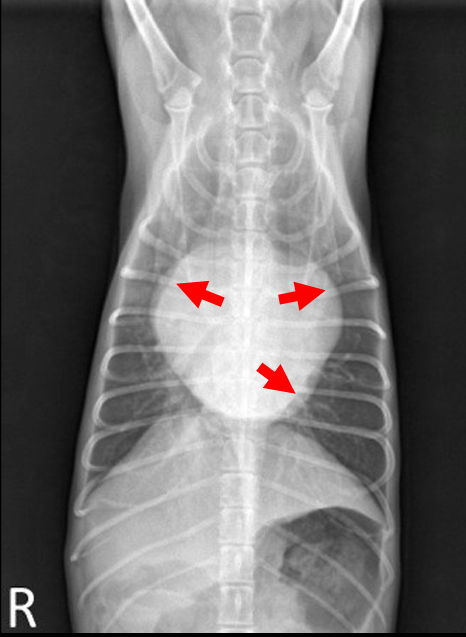

(CTR = chordae tendineae rupture), bivalvular

- Mitral & Tricuspid valve 모두 이상 ⇒ Lt. & Rt. atrium 모두 볼록

- Lt. auricle, LA 확장 ⇒ Trachea elevation, Caudal waist 소실, tall heart

☑️ 흉수(pleural effusion) : 우심부전 시 주로 흉수, 복수 (체순환 혈액 받아들이지X)

: 우심 valve 이상 → 폐로 가는 혈액량 감소 → 우심방 비대, 혈액 정체, congestion → 전신 정맥압 상승 → pleural cavity의 모세혈관 압력 증가, 수분 누출 → 흉막강에 체액 축적

⇒ 심장 주위 뿌옇게 물 참. 흉수 때문에 폐가 팽창하지 못해서(collapsed), 빈호흡, 호흡곤란, 산소 포화도 감소, 청색증 (*Thoracocentesis 필요)